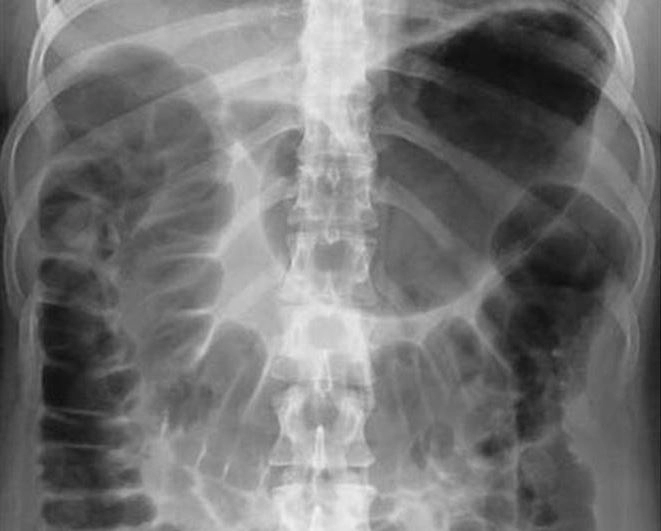

Рентген брюшной полости

Первоочередным методом обследования брюшины является рентгенография органов брюшной полости. При пропускании через тело пациента рентгеновских лучей на чувствительном экране формируется проекционное изображение внутренних органов, позволяющее судить о наличии патологических изменений. Поскольку мягкие ткани, как правило, плохо отображаются на снимках, для улучшения визуализации в организм иногда вводят контрастный раствор, который выделяет отдельные структуры. В качестве контраста обычно используются безвредные соединения бария.

Наиболее часто для определения причин недомогания требуется обзорная рентгенография брюшной полости, которая проводится без контрастных препаратов. Она позволяет обнаружить серьезные патологии, исключить некоторые из вариантов диагноза и определить направление дальнейших диагностических исследований. Процедура обычно проводится при наличии острых и неотложных состояний.

Рентгенография брюшной полости необходима в случаях, когда требуется оперативная информация о состоянии внутренних органов брюшины, т. е. в случае появления тревожных симптомов:

• острой боли в животе;

• болей в поясничном отделе;

• травмы живота;

• признаков забрюшинного абсцесса;

• подозрения на непроходимость кишечника;

• подозрения на наличие инородного тела.

Применение контрастного раствора в ряде случаев позволяет более точно определить причину появления болей, однако такое исследование проводится только при отсутствии внутренних повреждений и после исключения непроходимости кишечника.

• Что показывает рентген брюшной полости?

По рентгеновским снимкам опытный рентгенолог-диагност может определить:

• распределение газа в брюшине, наличие свободной жидкости в брюшной полости;

• наличие инородных тел;

• наличие конкрементов в почках и желчном пузыре;

• повреждения органов;

• внутренние кровотечения;

• смещение внутренних органов;

• непроходимость кишечника.